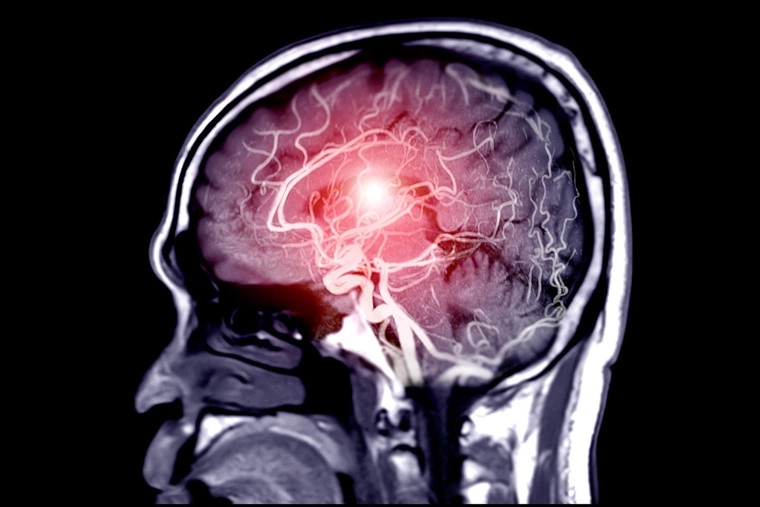

![]() |

| 24 giờ đầu tiên khi có triệu chứng đột quỵ là thời gian vàng để cứu chữa cho bệnh nhân. Ảnh: iStock. |